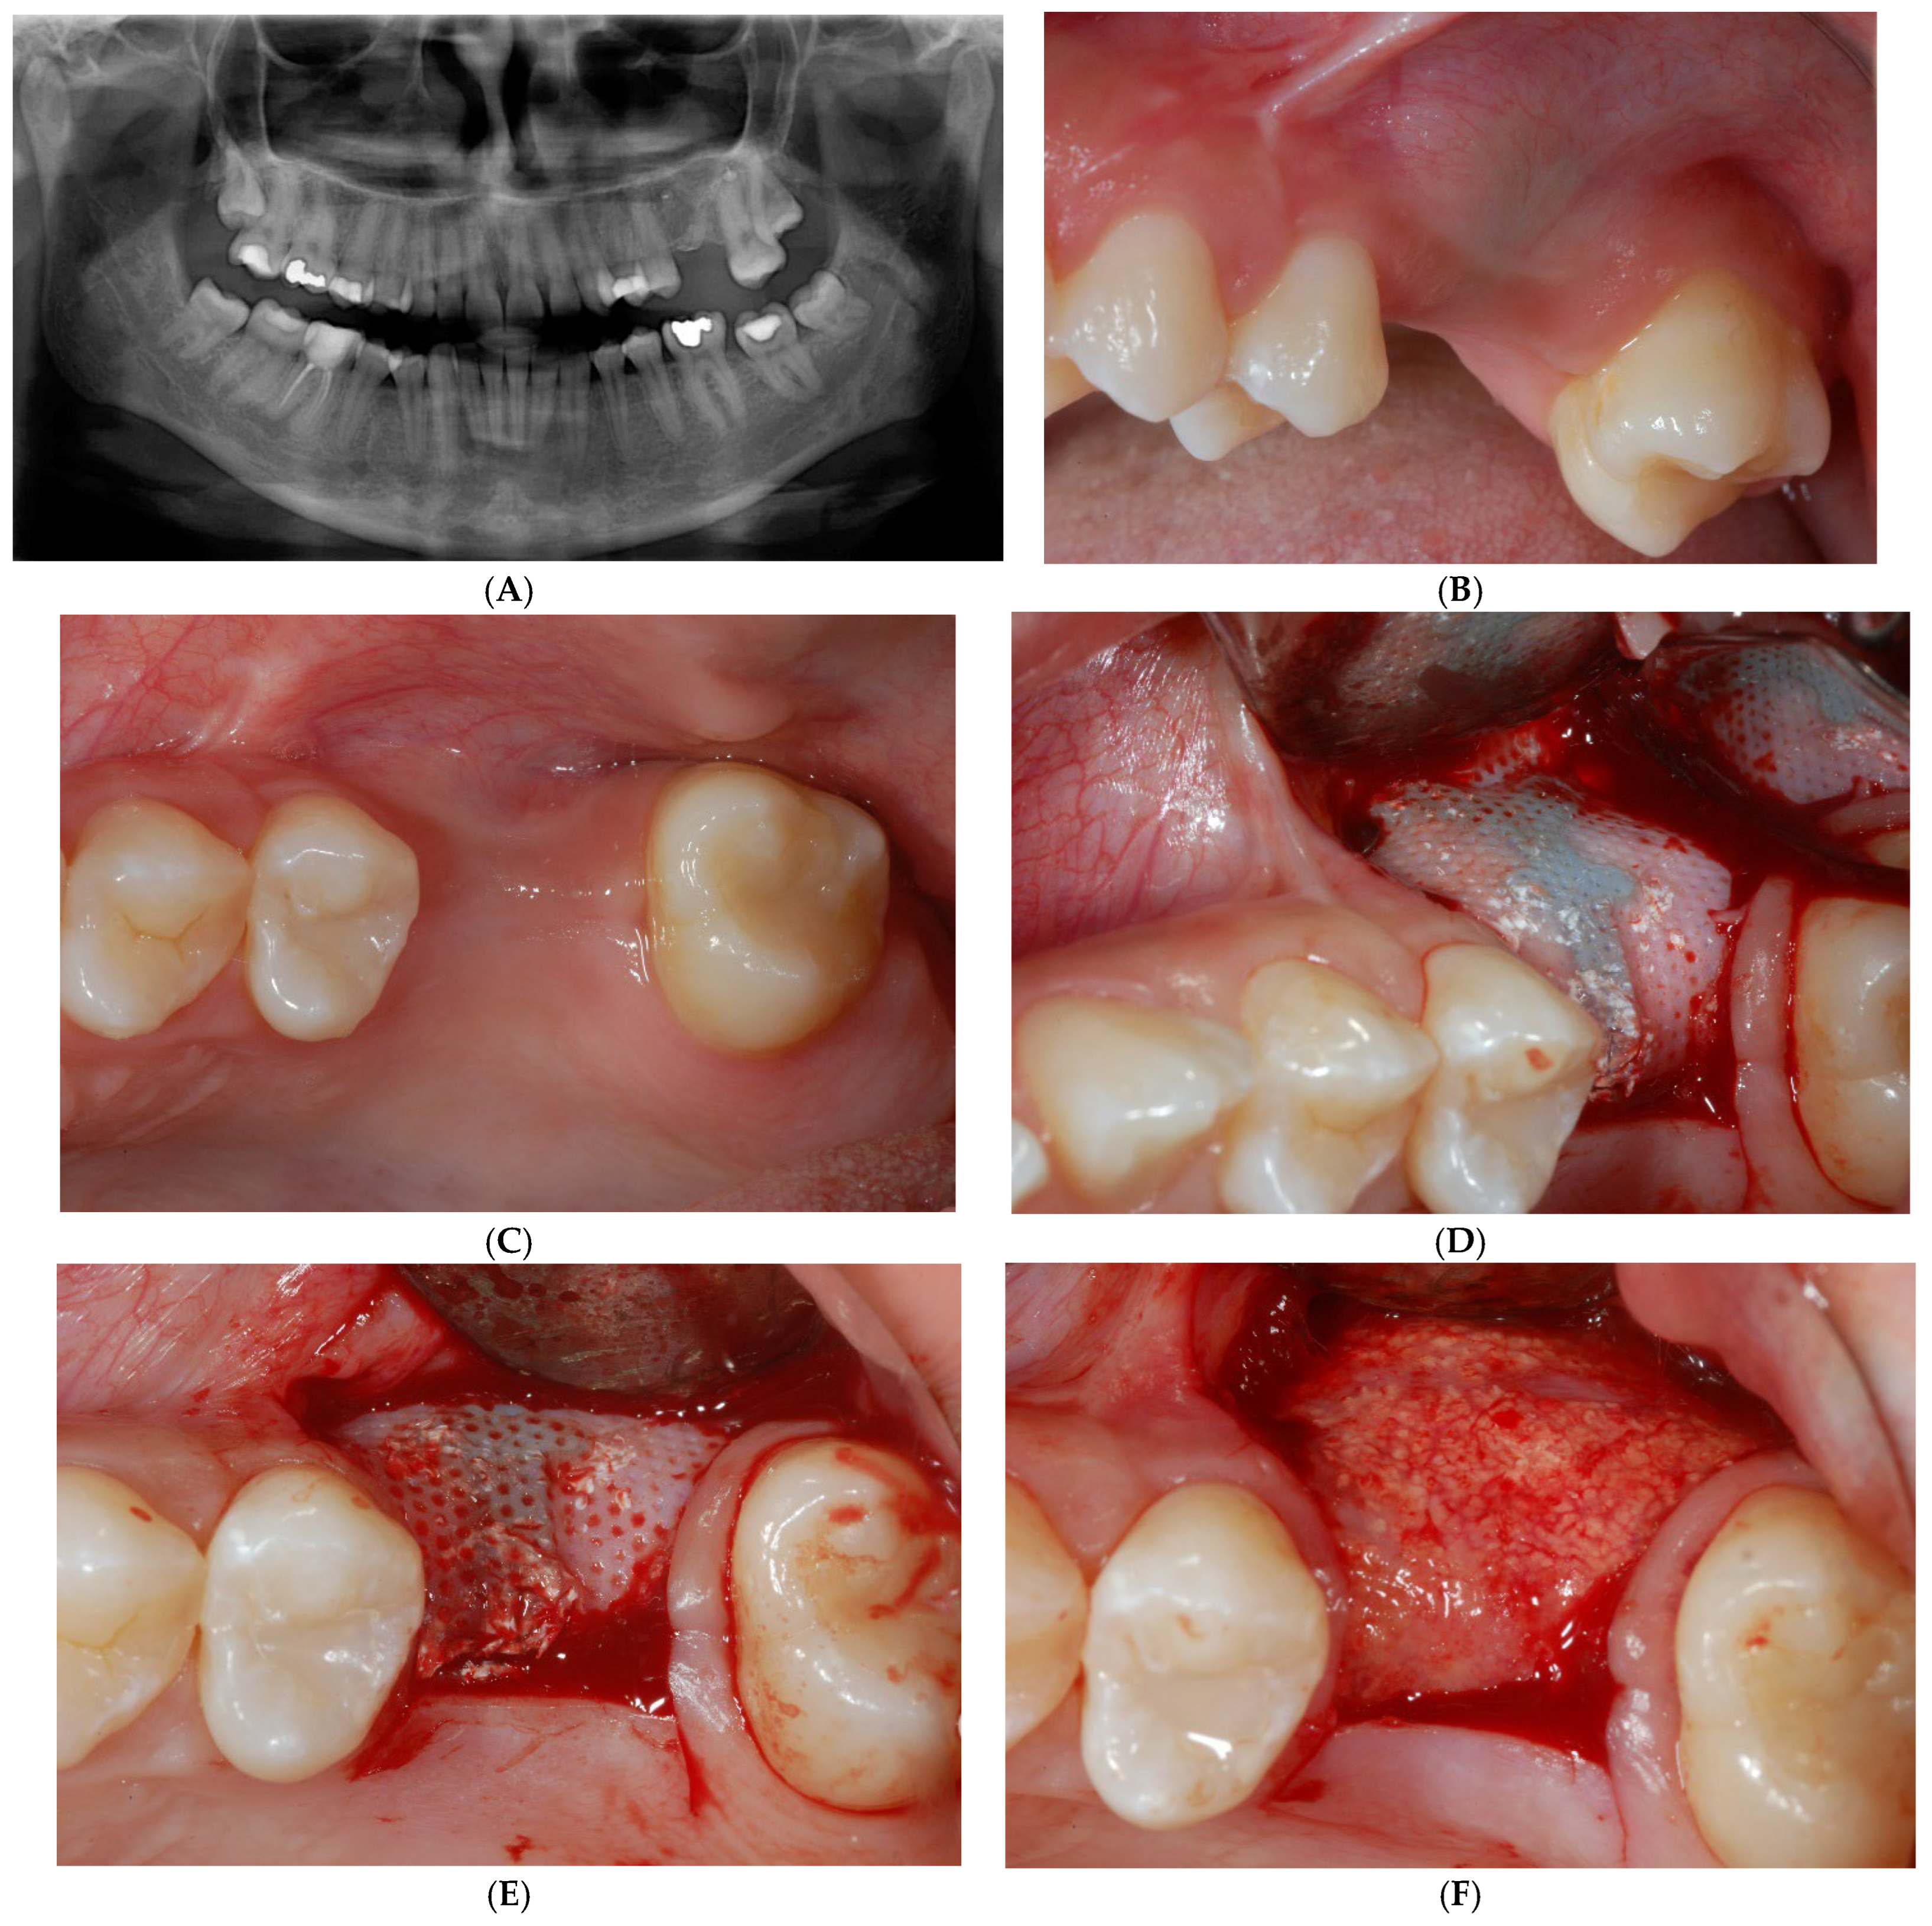

Figure 6.

Radiographic (A) and clinical (B,C) follow-up after a 10-month healing period. Site was re-opened for membrane removal and implant insertion. Smaller paramarginal trapezoidal mucoperiosteal flap, sparing the periodontum of adjacent teeth, was raised (D,E). Membrane was easily removed, and defect appeared completely regenerated (F).